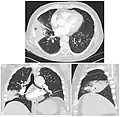

On a posteroanterior and lateral chest radiograph, an entire lobe will be radiopaque, which is indicative of lobar pneumonia.[5]

-

Chest radiograph of a lobar pneumonia, affecting the right middle lobe. -

CT scan of the same case.